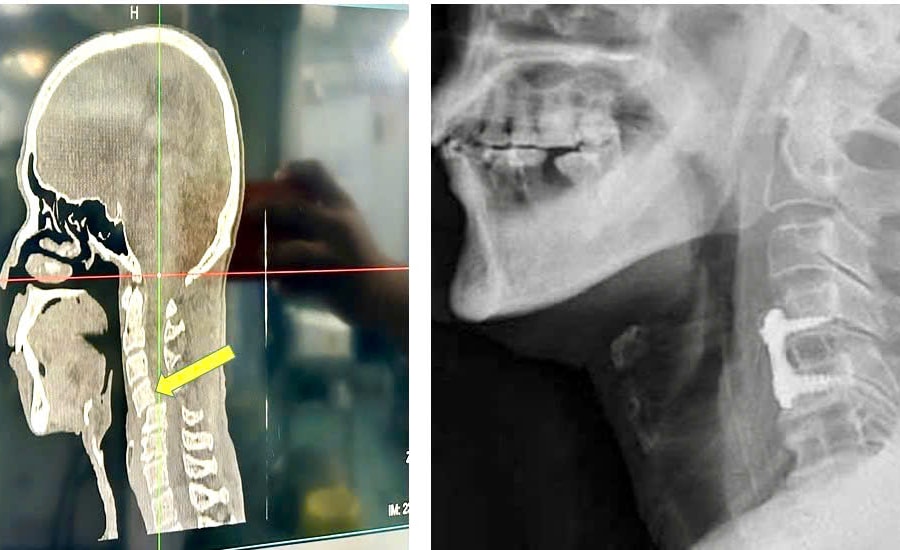

Thoát nguy cơ liệt tứ chi sau ca phẫu thuật trật đốt sống cổ hiếm gặp

Các bác sĩ vừa phẫu thuật thành công ca trật đốt sống cổ C45 hiếm gặp cho bệnh nhân 67 tuổi, giúp người bệnh thoát nguy cơ liệt tứ chi và hồi phục hoàn toàn vận động.